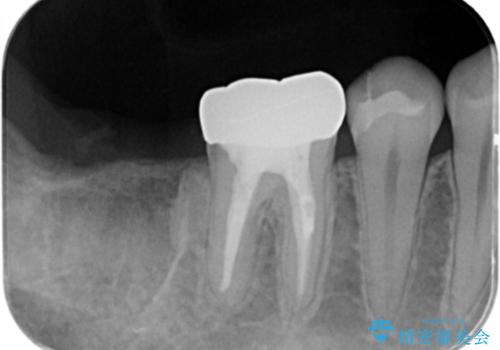

- 右下の奥歯がない状態でしばらく過ごされていた方です。

歯を抜いたまま放置してしまうと、その後の治療が困難になることがあります。

今回はかぶせ物の高さを確保するために、少し顎骨を削り、歯肉の厚みも薄くしました。